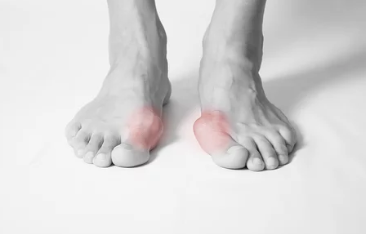

무μ§μΈλ°μ¦μ μμ§λ°κ°λ½μ΄ λ λ²μ§Έ λ°κ°λ½ μͺ½μΌλ‘ νμ΄μ§κ³ , μμ§λ°κ°λ½ κ΄μ μμͺ½μ΄ νμ΄λμ€λ μ§νμ λλ€.

- μμ§λ°κ°λ½ λ³ν: μμ§λ°κ°λ½μ΄ νμ΄μ§λ©΄μ λ° λͺ¨μμ΄ λ³νλκ³ , μ λ°μ μ μ λ λΆνΈν¨κ³Ό ν΅μ¦μ μ λ°ν©λλ€. μ λ μμ μλ νμ΄λμ¨ λΌ λλ¬Έμ μ λ°μ μ μ λλ§λ€ μμ²λ κ³ ν΅μ λκΌμ΅λλ€. π

- κ΅³μμ΄ & μΌμ¦: νμ΄λμ¨ λΌ λΆμμ κ΅³μμ΄μ΄ μκΈ°κ³ μΌμ¦μ΄ λ°μν μ μμ΅λλ€.